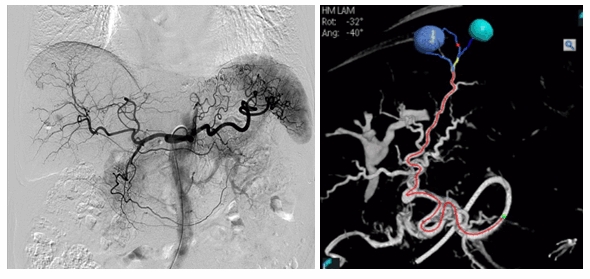

血管狭窄に対する血管形成術(PTA)や、外傷などによる血管損傷に対する血管塞栓術など多岐にわたり、ほぼ全身の血管系IVRを行っています。肝動脈化学塞栓術(TACE)ではEmboGuidを使用し腫瘍の栄養血管を3Dロードマップを使いセレクティブ的に選択して腫瘍だけにお薬を注入し治療をおこなっています。栄養血管をより迅速にかつ正確に検出するソフトウェアが導入され、より精度の高いカテーテル治療を提供できるように行っています。